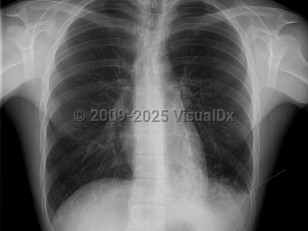

Primary viral pneumonia is the complication responsible for the most influenza-related deaths. Those with pre-existing cardiopulmonary disease or who are pregnant are at the greatest risk. The initial clinical presentation is the same, but dyspnea increases in severity. Productive cough may be blood tinged. Massive hemoptysis has been reported. When severe, there may be profound respiratory distress with tachypnea, tachycardia, and cyanosis. Rales and wheezes will spread throughout the chest from the lower lung.